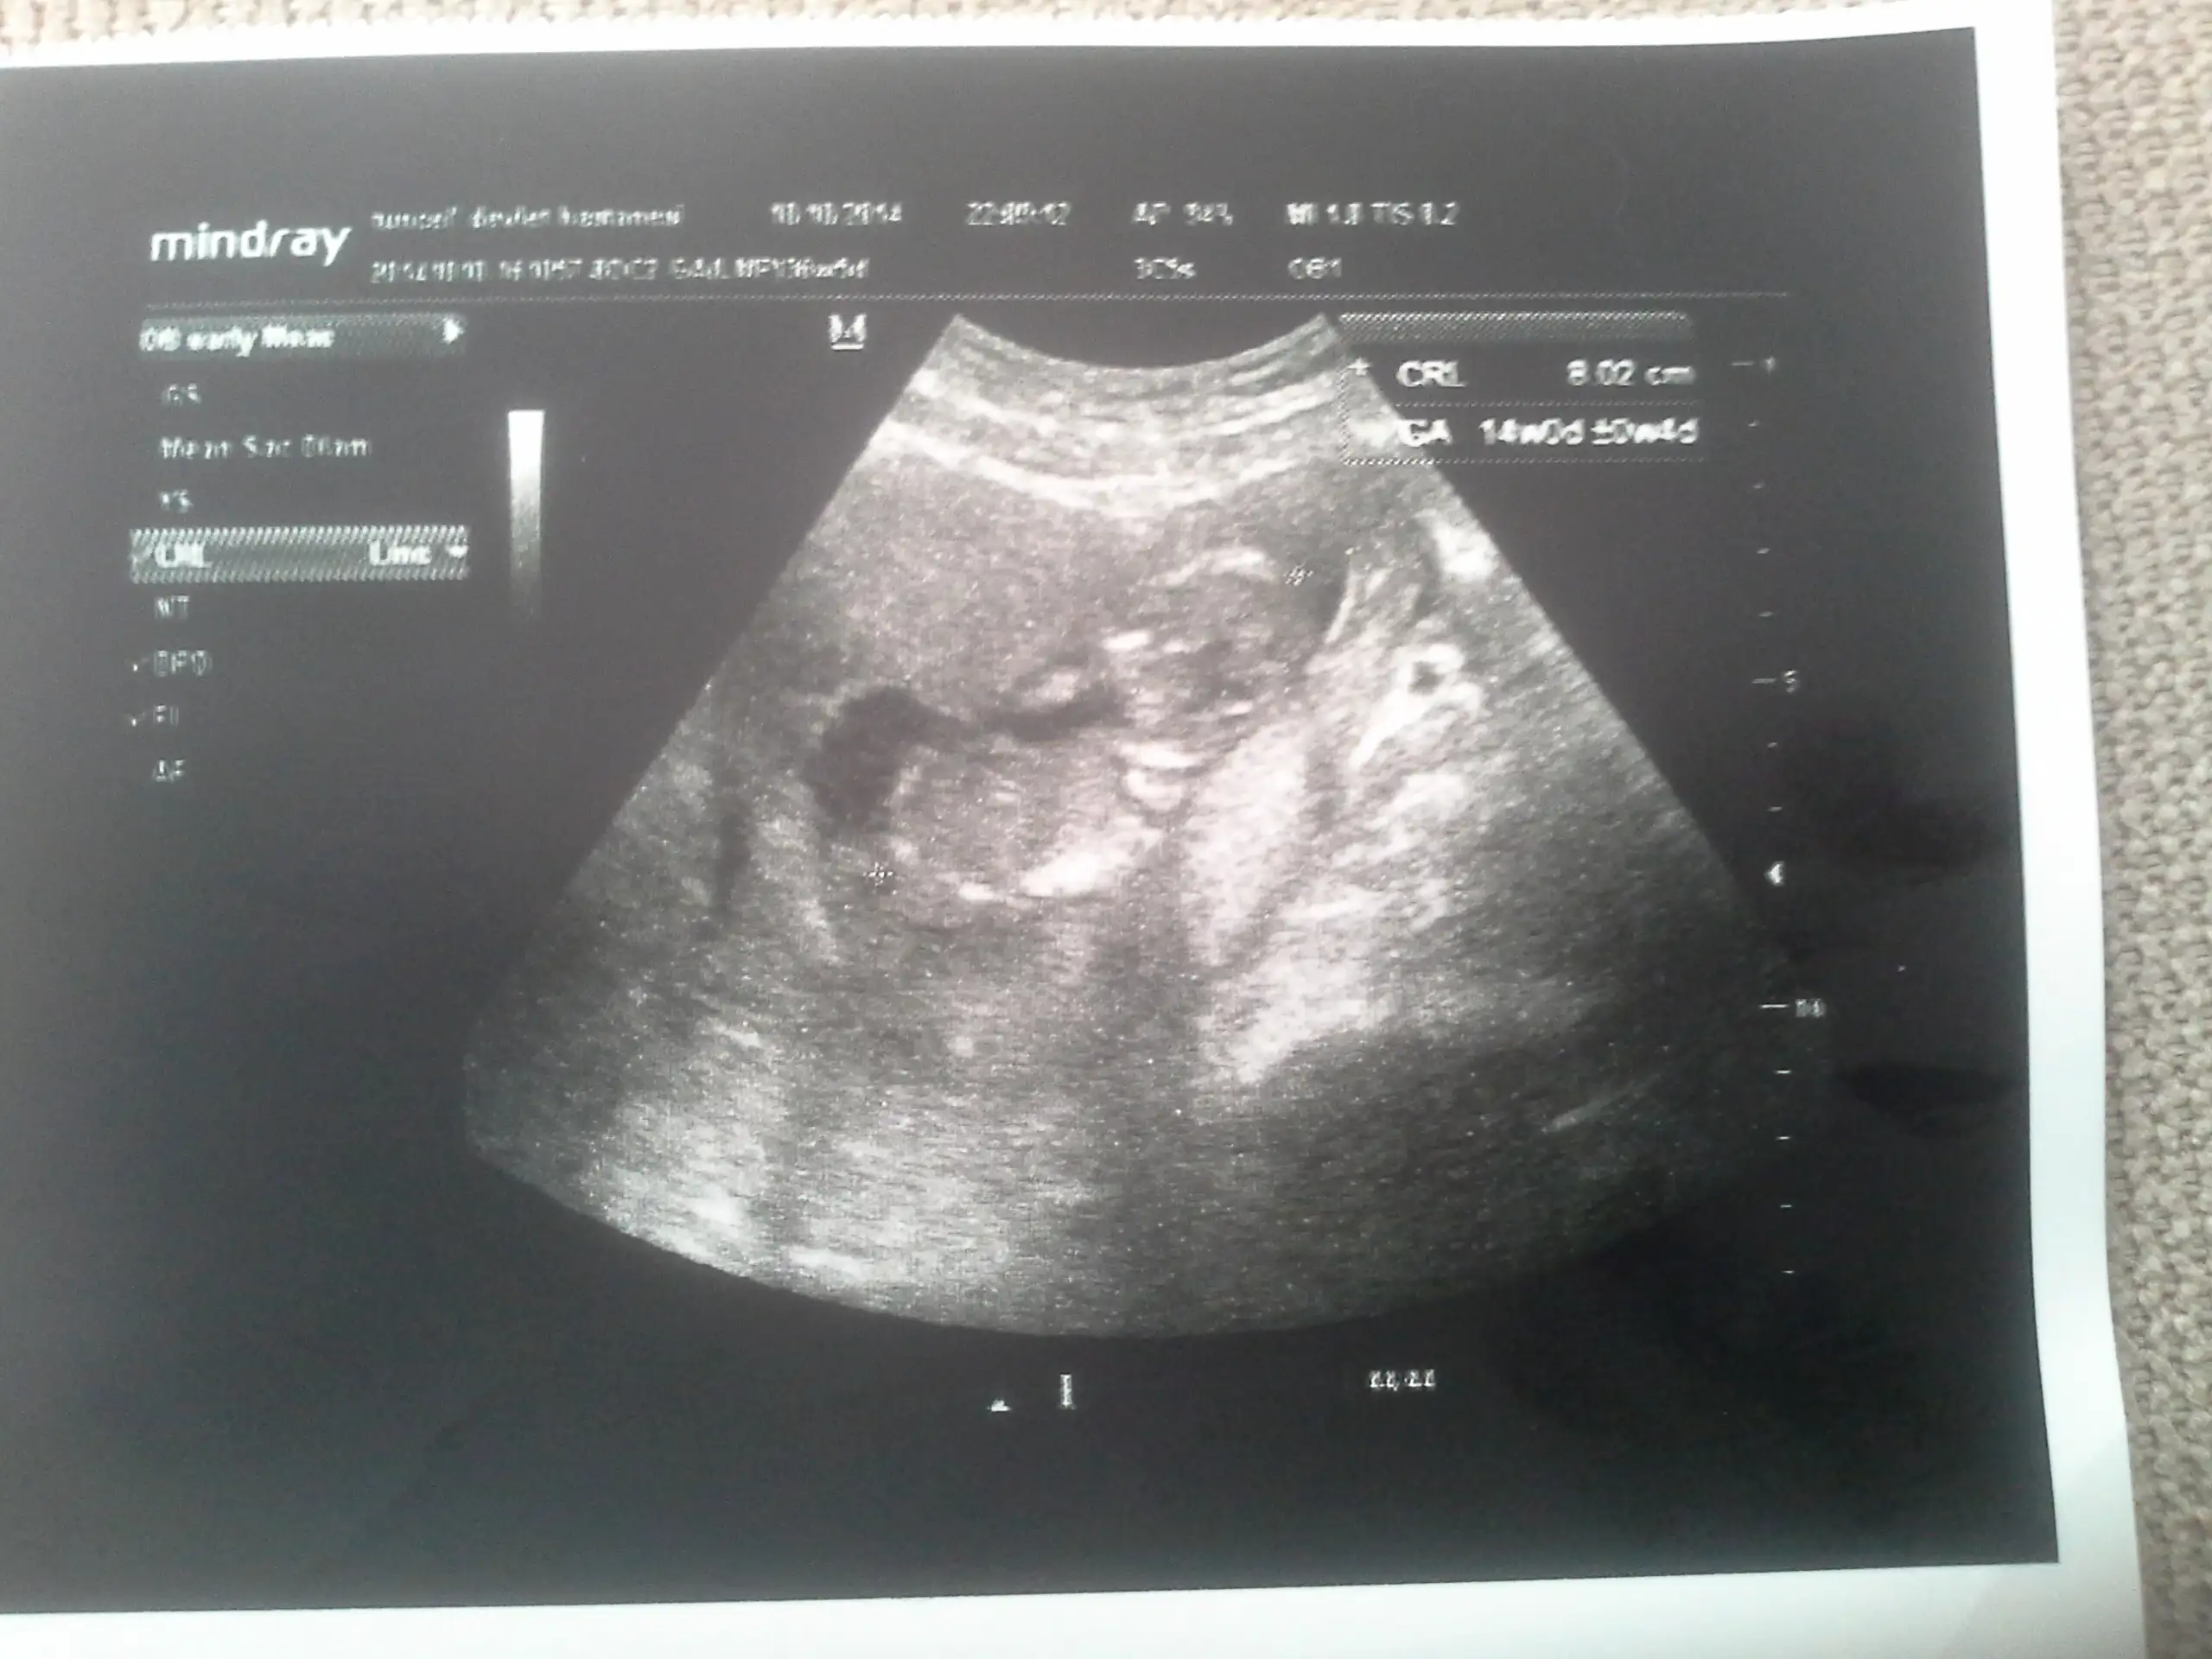

fotoların açısı çok kötü ama kaç haftalık oda önemli 13 lerdeyse kız gibi

Evt 13 +5 teyz cok merak ediyrm ya doktor soylemedi daha erken dedifotoların açısı çok kötü ama kaç haftalık oda önemli 13 lerdeyse kız gibi

bu kız gibi bu varsayıma göre

Kizlar bgn tam 16 haftaligiz

Doktorum tam net olmamakla birlikte bi tahmin ypti.siz ne diyorsunuz? Nolur bse diyin